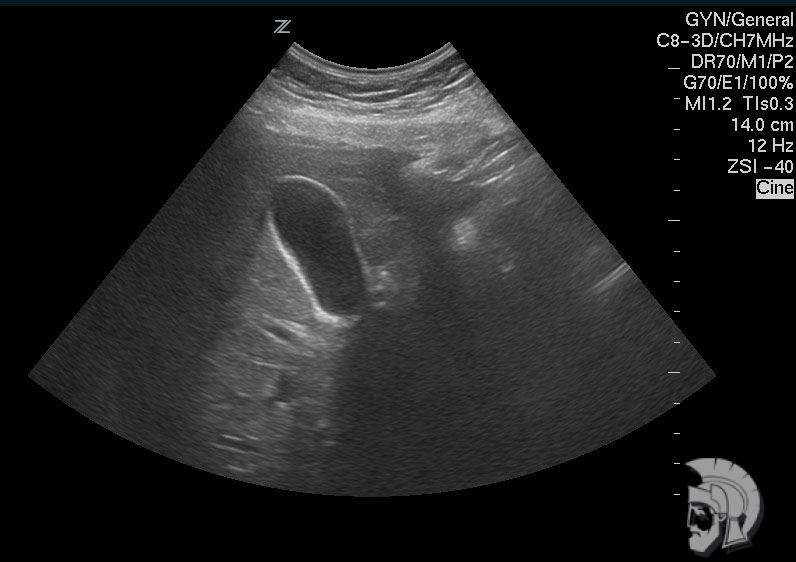

| Фото желчного пузыря. Перетяжка в нижней трети желчного пузыря мужчины 43 лет |

| 3D-фото желчного пузыря. Тот же случай |